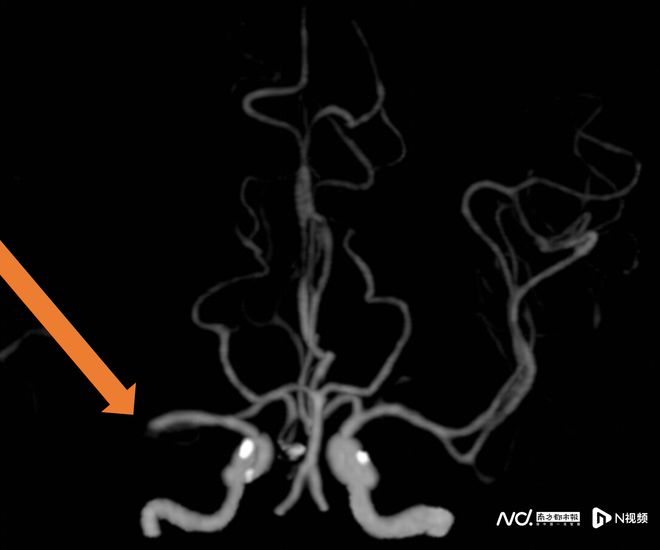

近年來,卒中發病呈現年輕化趨勢。數據顯示,55歲以下患者比例上升了40%。專家分析,除了高血脂、肥胖、痛風等基礎疾病,運動不足、壓力過大、高鹽高糖飲食等不良生活習慣也是主要原因。值得注意的是,三位專家均表示,大力按摩頸部導致血管夾層,已成為年輕人卒中的上升誘因之一。

此外,長期口服避孕藥、年輕時有偏頭痛史未干預、睡眠呼吸暫停等,也增加了年輕人卒中風險。專家呼吁年輕群體重視體重管理、規律運動、緩解壓力、足量飲水,并避免非專業指導下的頸部暴力按摩。